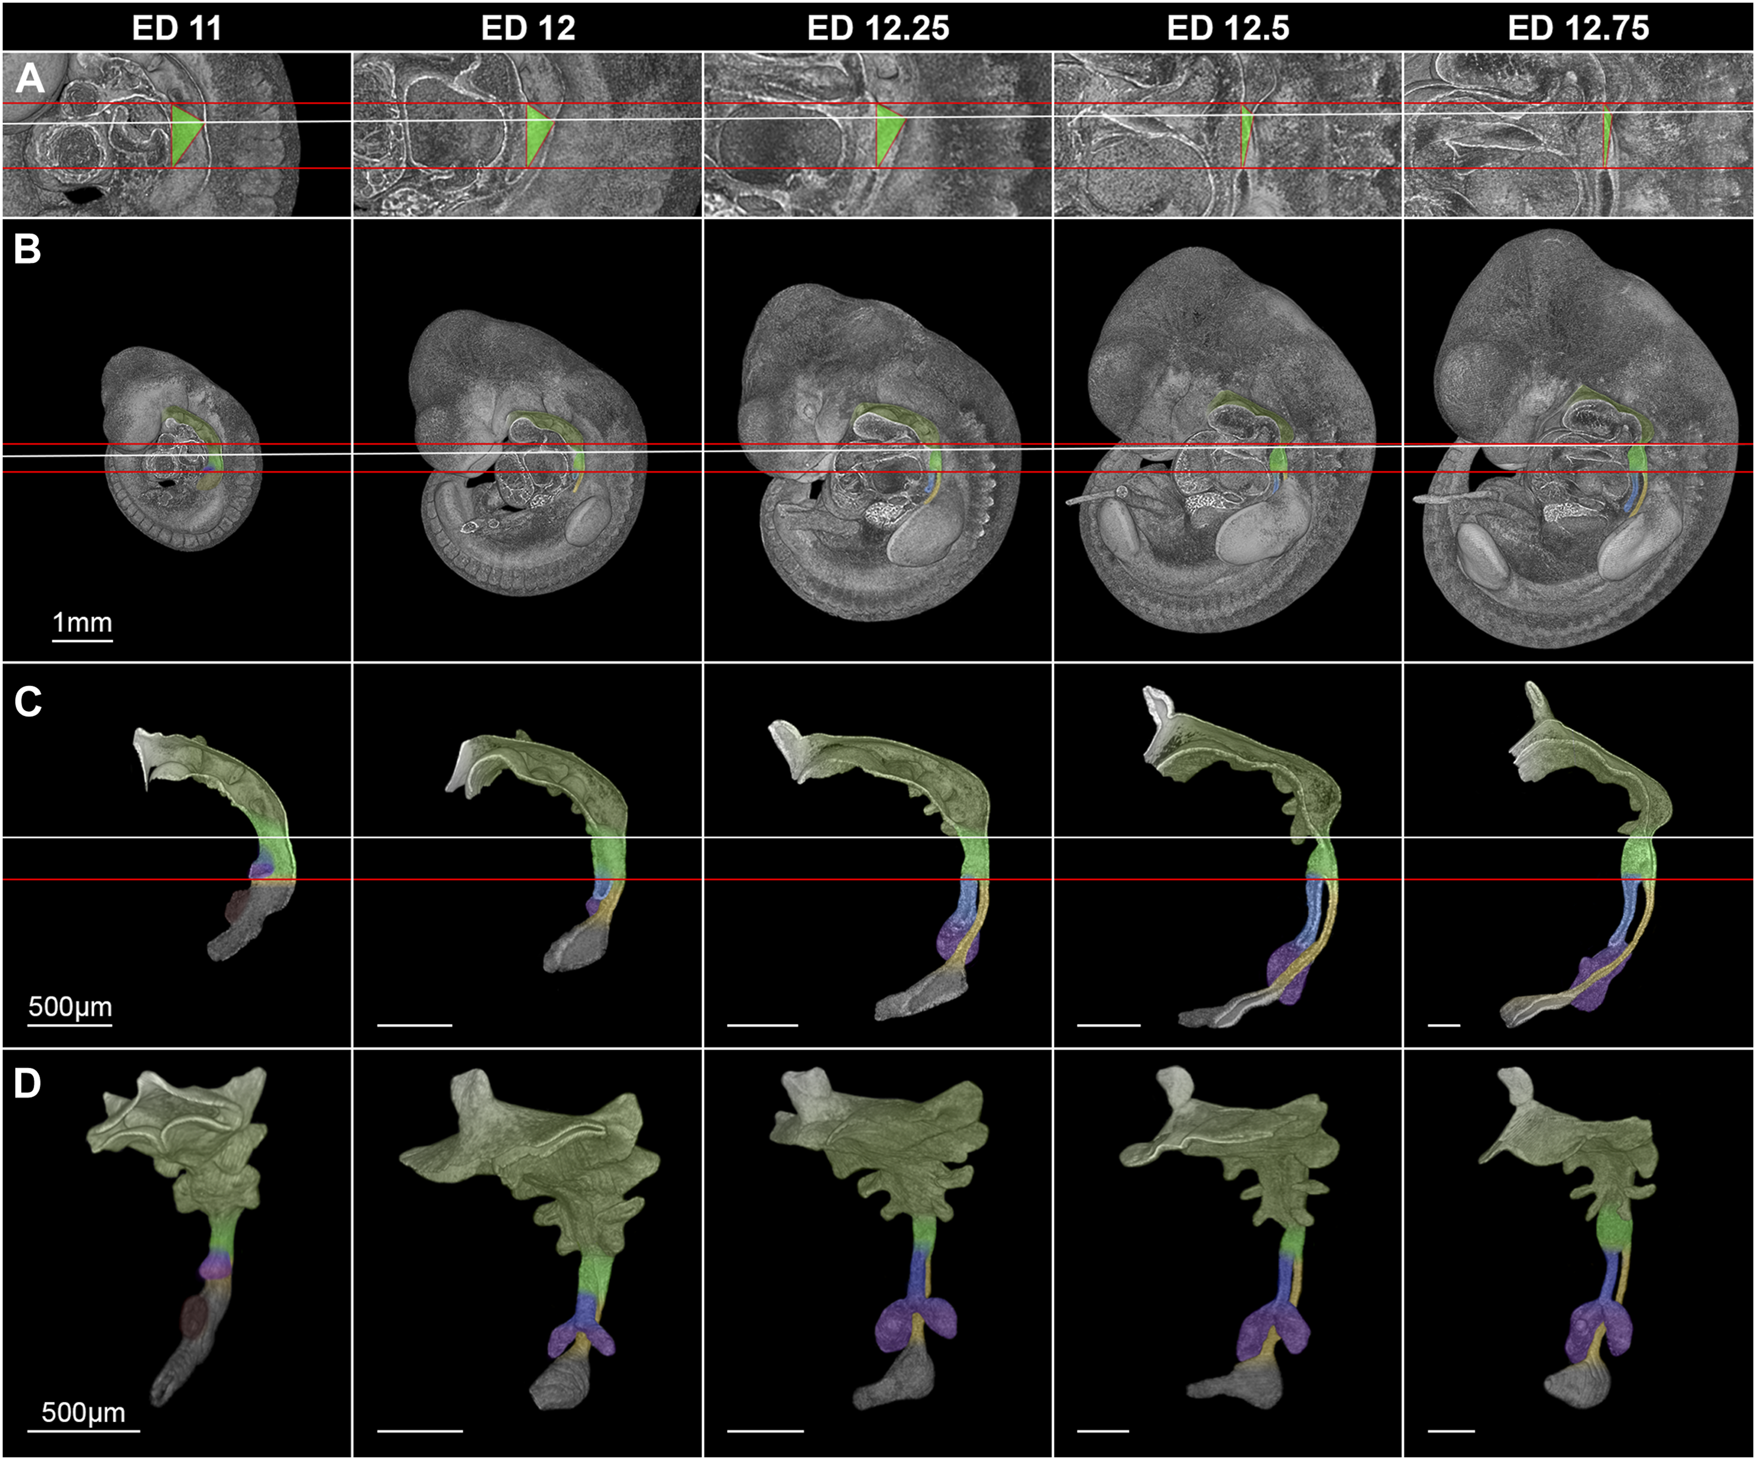

In rat embryos, the lung buds formed at embryonic day (ED) 11 as ventral protrusions from the tracheoesophageal region of the foregut cranial of and in direct contact with the developing stomach (Figure 3). This fold caused by the lung buds marks the TE bifurcation and thus the starting point of tracheal development. 130 µm caudally of the lung bud the liver primordium formed another ventral bud from the developing stomach (Figure 3). At ED 12, a small portion of the trachea and esophagus has developed, and the liver primordium has differentiated into liver. In rats, it takes only one more day to form a distinct portion of the trachea and esophagus. Thus, we took samples every quarter day for a better resolution, referring to it as ED 12.25, ED 12.5 and ED 12.75. We analyzed the morphology and morphometry at these time points of the intermediate foregut compartment and the trachea and esophagus.

FIGURE 3

Morphological growth dynamics of the intermediate compartment of the foregut, the trachea and esophagus from ED 11 to ED 12,75. (A) The caudal, ventrocranial and dorsocranial measurement points for the intermediate compartment. (B) Rat embryos with a virtually broached foregut to scale. (C) Sagittal view on virtually excised foreguts including the trachea, esophagus and stomach. (D) Front-left view on the whole excised foreguts. The horizontal red lines indicate the height of the ventrocranial end of the intermediate compartment to the TE bifurcation point (distance ∼410 µm), while the white line shows the dorsocranial end of the TE foregut. Light green: Intermediate foregut compartment, blue: Trachea, yellow: Esophagus, purple: Lung, dark green: Upper foregut compartment (Pharyngeal foregut), dark gray (C,D): Stomach.

Morphologically, the TE bifurcation point defined the caudal border of this intermediate compartment. Additionally, we found a cranial border, which can be identified by a dorsal and ventral epithelial fold, connected by lateral folds. The dorsal fold was located in the area between the 3rd and 4th somites, the ventral fold approximately at the area of the 4th pharyngeal pouch (Supplementary Figures S1–S5). From ED 11 to ED 12.75, these folds converged by a dorsal movement of the ventrocranial fold (Figures 3A, B), thereby narrowing the foregut in this region and forming the cranial entrance from the pharynx into the developing larynx—hypopharynx (Figures 3C, D). The dorsal wall of the pharynx also folded into dorsal direction in this period (Figure 3). At around ED 12.5 the differentiation of the intermediate compartment of the foregut into the larynx (ventral) and hypopharynx (dorsal) was visible by lateral mesenchymal thickening, which continued over time. Our measurements supported these observations. The most ventrocranial point of the intermediate compartment remained at a constant distance of 410,5 µm (±3.8 µm) to the TE bifurcation point from ED 11 to ED 12.75, but moved in dorsal direction, thereby narrowing the pharynx—larynx transition zone from 281.8 µm (±4.8 µm) to 74.9 µm (±13.6 µm). The most dorsocranial point of the intermediate compartment increased its length linear from 282.5 µm (±11.9 µm) at ED 11–369.1 µm (±20.1 µm) at ED 12.75 (Figure 4A). The object volume increased linear from 7.8 µm (±1.1 µm) to 22.1 µm (±0.6 µm) (Figure 4B). However, the luminal volume (total volume minus object volume) decreased from 1.69 µm (±1.1 µm) at ED 11 to 0.37 µm (±0.13 µm) at ED12.5 and increased after that to 1.09 µm (±0.47 µm) at ED 13 (Figure 4C).

For the cranial end of the intermediate compartment of the foregut, e.g., the 4th pharyngeal pouch was used in previous studies (Qi and Beasley, 2000). In our study, we morphologically identified two landmarks from ED 11 to ED 12.75 (the dorsal and ventral epithelial fold), which we measured. We found that the ventral length differs from the dorsal length. The distance between the TE bifurcation point and the ventrocranial endpoint remained constant from ED 11 to ED 12.75, while the distance between the TE bifurcation point and the dorsocranial endpoint was increasing linear in this period. In addition, we measured the distance between these two cranial endpoints and found that the distance shortens over time by a dorsal movement of the ventrocranial endpoint, thereby forming the cranial entrance into the developing larynx—hypopharynx (Figures 3, 4). This means, that a shorting of the distance between the TE bifurcation point and the cranial endpoints of the intermediate compartment does not take place, refuting the ideas of a complete or partial splitting or dividing of a “common” foregut tube.